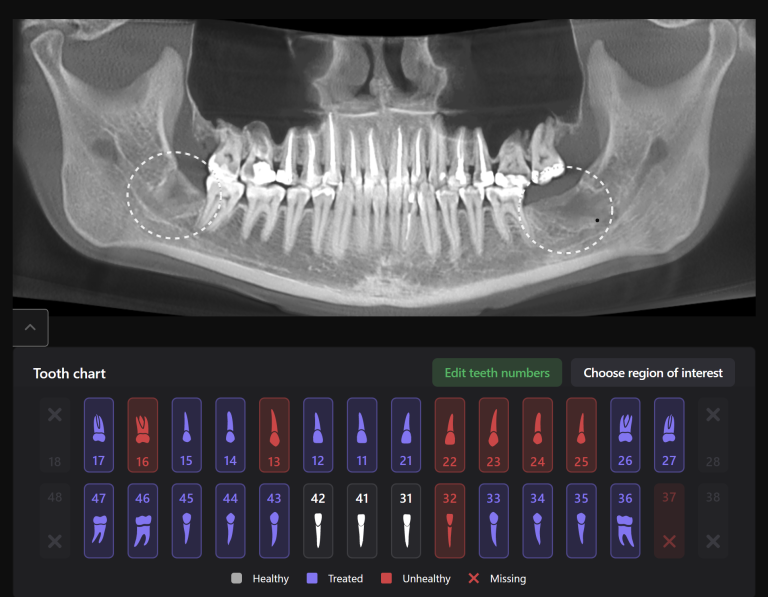

Diagnocat is an artificial intelligence system, one of its advantages being assistance in planning therapeutic dental treatment and identifying signs of caries

Diagnocat determined not only the presence, but also the localization of the focus of radiolucency of enamel and dentin, which was correctly indicated as “signs of caries” in the report

The presence of a structured report allows the clinician to set up the patient for timely treatment and build a consistent plan for therapeutic dental treatment